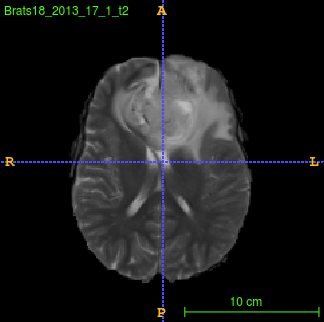

Segmentation of brain tumor from magnetic resonance imaging (MRI) is a vital process to improve diagnosis, treatment planning and to study the difference between subjects with tumor and healthy subjects. In this paper, we exploit a convolutional neural network (CNN) with hypercolumn technique to segment tumor from healthy brain tissue. Hypercolumn is the concatenation of a set of vectors which form by extracting convolutional features from multiple layers. Proposed model integrates batch normalization (BN) approach with hypercolumn. BN layers help to alleviate the internal covariate shift during stochastic gradient descent (SGD) training by zero-mean and unit variance of each mini-batch. Survival Prediction is done by first extracting features(Geometric, Fractal, and Histogram) from the segmented brain tumor data. Then, the number of days of overall survival is predicted by implementing regression on the extracted features using an artificial neural network (ANN). Our model achieves a mean dice score of 89.78%, 82.53% and 76.54% for the whole tumor, tumor core and enhancing tumor respectively in segmentation task and 67.90% in overall survival prediction task with the validation set of BraTS 2018 challenge. It obtains a mean dice accuracy of 87.315%, 77.04% and 70.22% for the whole tumor, tumor core and enhancing tumor respectively in the segmentation task and a 46.80% in overall survival prediction task in the BraTS 2018 test data set.